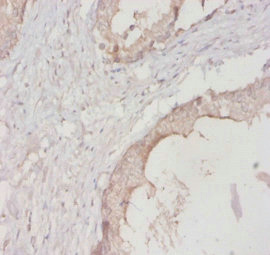

Immunohistochemistry of paraffin-embedded human prostate tissue using CSB-PA02174A0Rb at dilution of 1:20